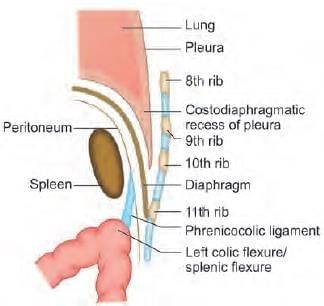

A 25-year-old male presents to emergency with left upper quadrant pain, upon examination spleen was measured to 20 cm and further extending to the mid umbilicus. The extension of the spleen to left lower quadrant was prevented by: (NEET-PG 2021)